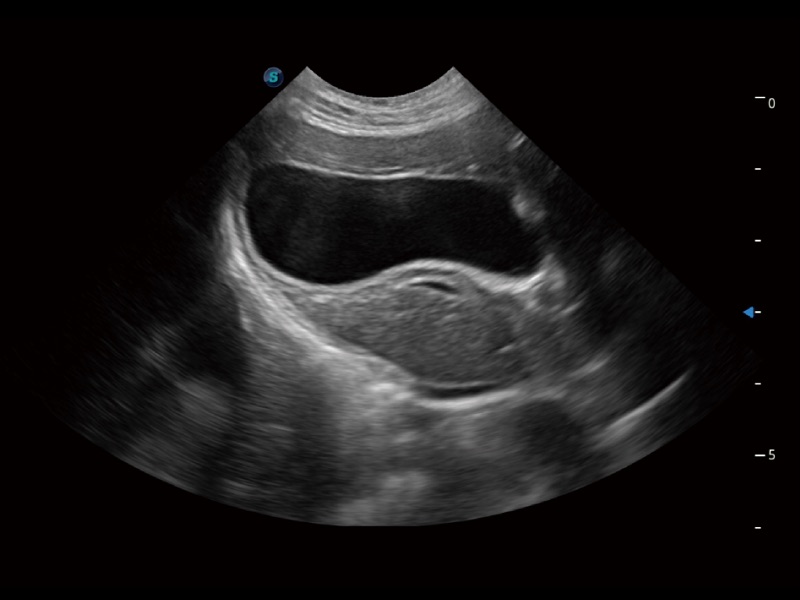

(猫)胆囊

(犬)四腔心

优异的基础图像

ProPet 70 全新的动物超声智能软件和丰富的探头群,为动物医生提供了高清晰度和精细分辨率的图像,无论在宠物、马科、畜牧还是实验室动物等应用中都可以轻松应对,为您的日常工作带来满意的体验。